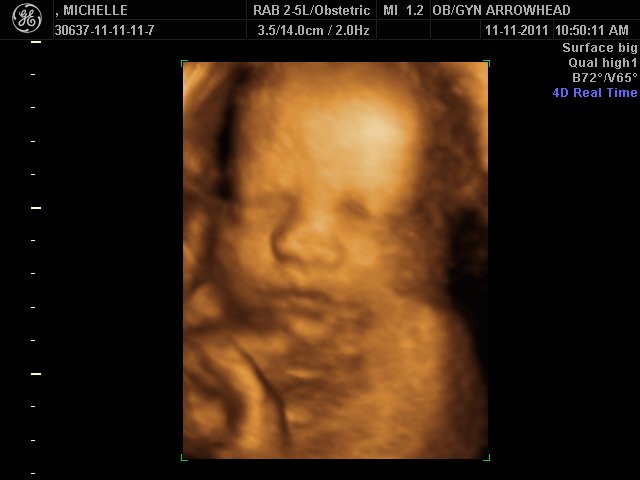

We offer complimentary 3D/4D Ultrasounds to all our OB patients around 30 weeks! The following photos are some examples of our work, shown with permission from our patients.